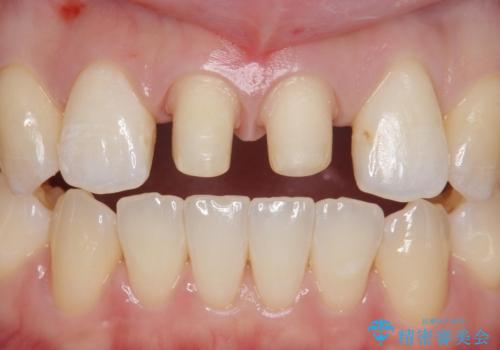

前歯を綺麗にしたい。

- 前歯の審美性改善と、軽度のがたつきを主訴に来院された患者様です。

マウスピース矯正を行った後、かぶせ物で審美性を改善していきます。